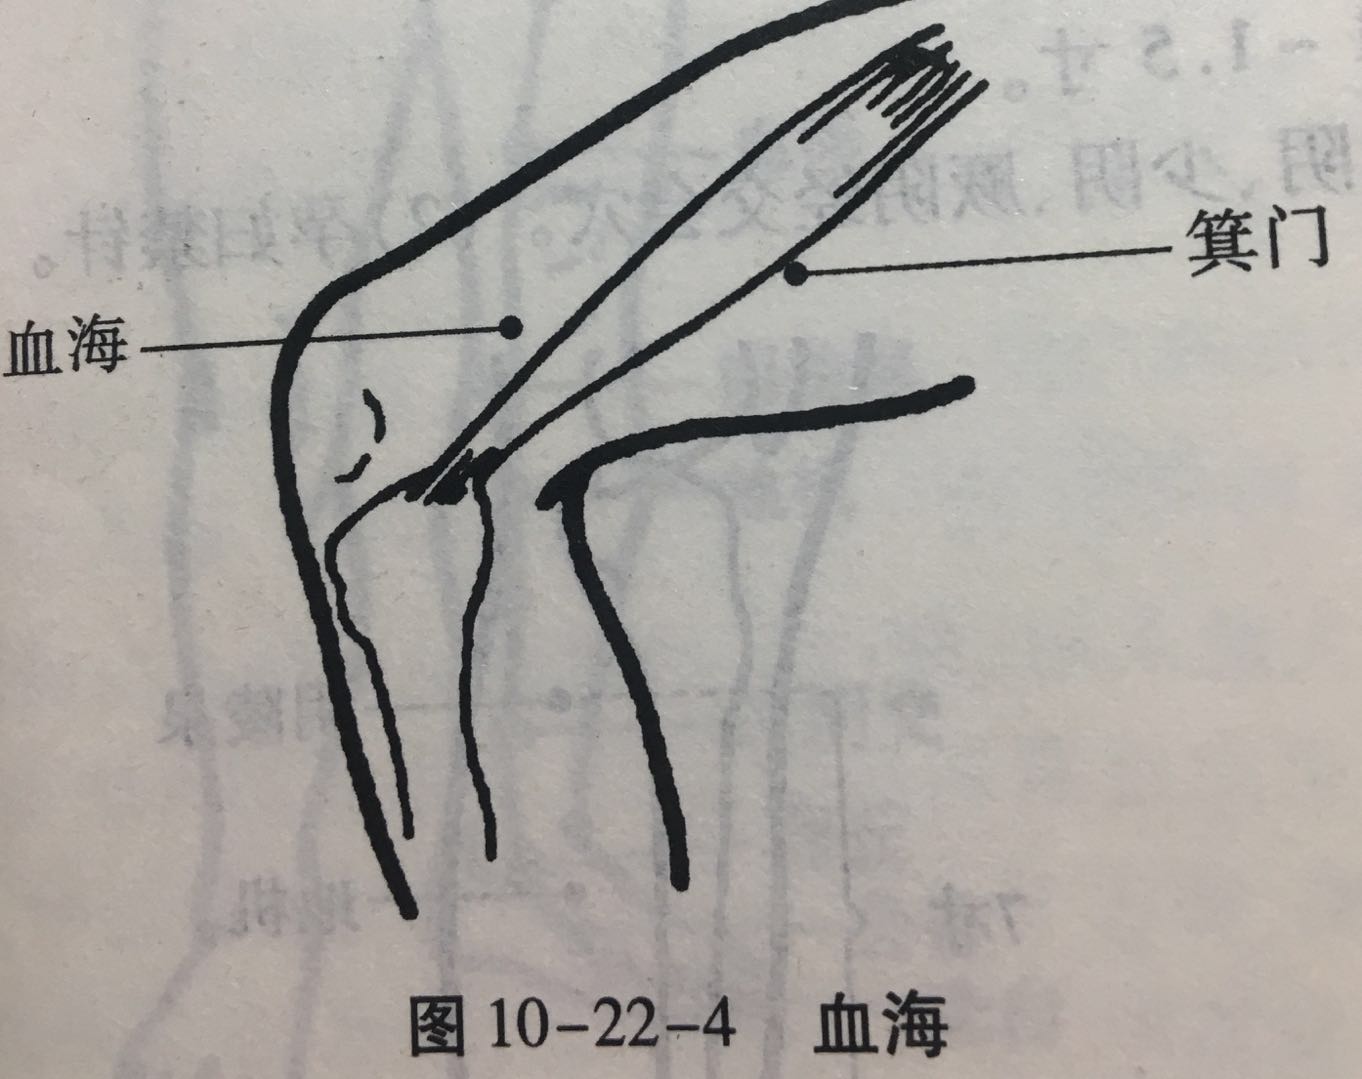

血海

【定位】 屈膝,在大腿内侧,髌(bìn)骨内上缘上 2 寸,当股四头肌内侧头的隆起处(图 10-22-4)。

简便取穴:患者屈膝,医者以左手掌心按于患者右膝髌骨上缘,2 至 5 指向上伸直,拇指约呈 45 度斜置,拇指尖下是穴。对侧取法仿此。

【主治】 月经不调,崩漏,经闭,瘾疹,湿疹,丹毒。

【配伍】 配三阴交治月经不调,配曲池治瘾疹。

【刺灸法】 直刺 1 ~ 1.5 寸。